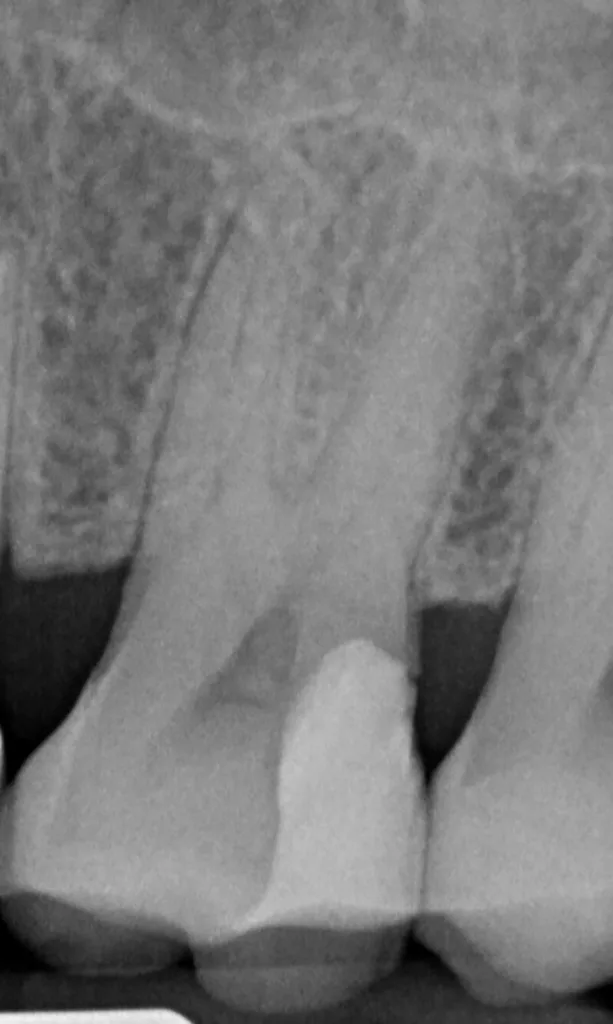

Die selektive Kariesexkavation wurde in den letzten Jahren als eine potenziell vielversprechende Alternative zur vollständigen Exkavation des kariösen Gewebes propagiert. Grundannahme hierbei ist, dass eine Exposition der Pulpa im Rahmen der Kariesexkavation vermieden werden sollte, um die Pulpa vital zu erhalten. Ziel dieser Methode ist es, eine invasivere Behandlung wie eine direkte Überkappung, eine partielle oder vollständige Pulpotomie oder sogar eine Wurzelkanalbehandlung zu vermeiden. Voraussetzung für die Durchführung der selektiven Kariesexkavation ist, dass der betreffende Zahn klinisch und radiologisch symptomfrei ist (keine Schmerzen, keine apikalen Pathologien) und im Röntgenbild eine verbleibende Hartgewebsbrücke zwischen der kariösen Läsion und der Pulpa zu sehen ist [15].

Wird eine profunde kariöse Läsion behandelt, empfiehlt sich folgendes Vorgehen [5]: Zunächst sollte in einem ersten Schritt ein Kofferdam appliziert werden, um eine möglichst keimfreie Arbeitsweise zu gewährleisten. Nach Präparation einer Zugangskavität, wenn dies notwendig ist, erfolgt die Kariesexkavation mittels Rosenbohrern oder Handexkavatoren. Wird in pulpanahen Arealen eine Eröffnung der Pulpa erwartet, sollte das Instrument gewechselt und ein sauberer Rosenbohrer genutzt werden. Tritt nach vollständiger Kariesexkavation keine Eröffnung der Pulpa ein, ist aber von einer dünnen Restdentindicke von etwa 300 µm auszugehen, oftmals erkenntlich durch eine zartrosa hindurchschimmernde Pulpa, sollte nach Kavitätentoilette mittels Natriumhypochlorit (NaOCl) 3% eine indirekte Überkappung mit einem hydraulischen Kalziumsilikatzement erfolgen [5]. NaOCl dient dazu, Bakterien und Toxine zu neutralisieren und das Dentin zu desinfizieren. Die Unterfüllung aus Kalziumsilikatzement soll auch desinfizierend wirken, das Pulpagewebe zur Heilung anregen und vor möglicherweise durch das Dentin penetrierenden Monomeren aus dem Dentinadhäsivsystem schützen [5], da diese die regelrechte Funktion der Odontoblasten beeinträchtigen können [9,40]. Im Anschluss muss eine direkte, dentinadhäsive Restauration zur Versorgung der Kavität platziert werden [5]. Die Abbildungen 1 bis 14 illustrieren das Vorgehen bei der Behandlung einer profunden kariösen Läsion mit indirekter Überkappung der Pulpa.